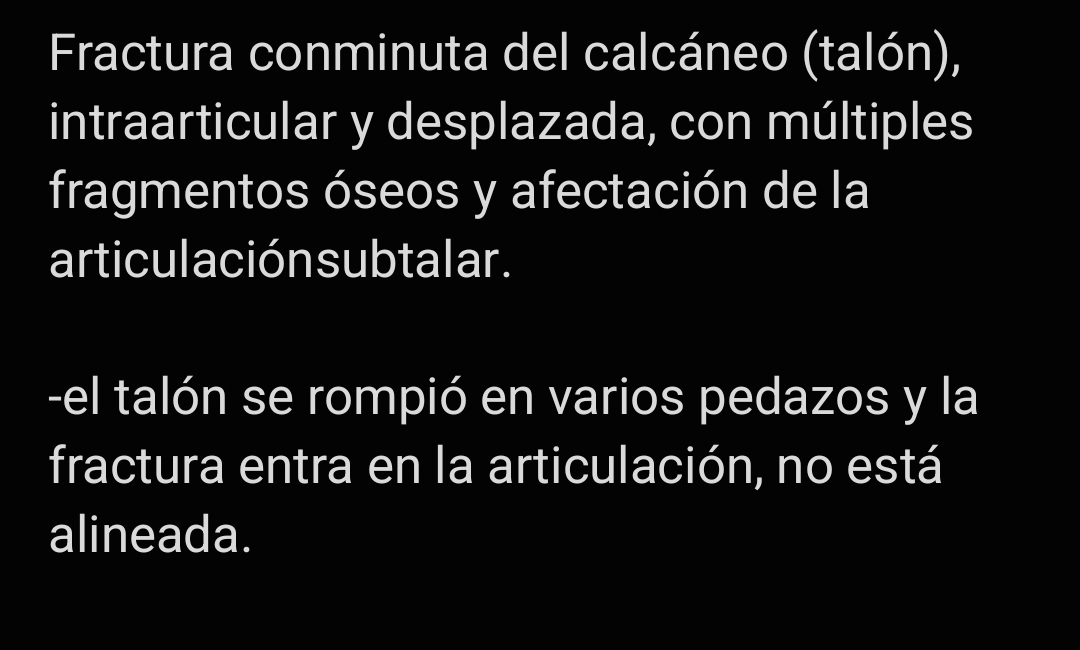

This is a crucial step toward my recovery and getting back to a normal life. Beyond the procedure itself, there are ongoing medical expenses, medications, post-operative care, and the financial strain of being out of work during recovery.